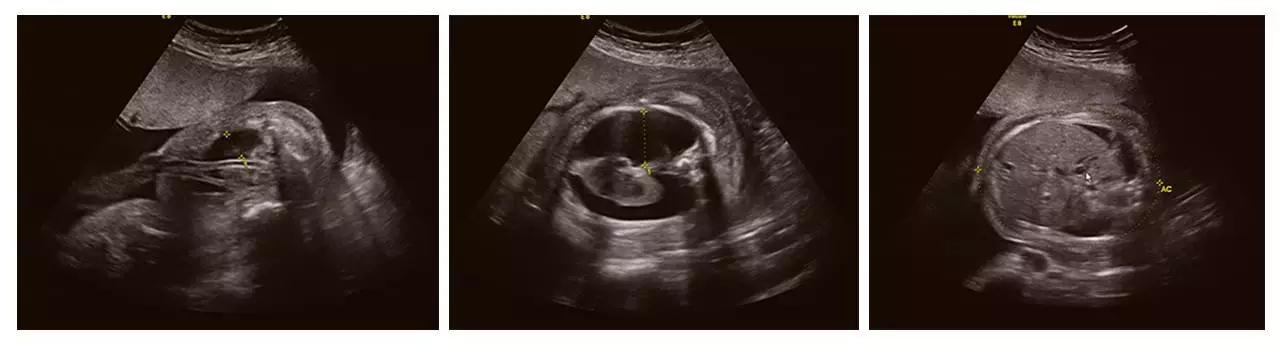

济南艾玛妇产医院引进的GE高清四维彩超(四维彩超)设备,是目前世界上先进的彩色超声设备,远比普通超声设备清晰、准确,被誉为"神奇彩超",是产前筛查的尖端设备,能够多方位、多角度地观察宫内胎儿的生长发育情况,为早期诊断胎儿先天性体表畸形和发育异常提供科学依据,以便尽早的进行治疗。有效防止和减少新生儿出生缺陷的发生。

美GE不仅能提供包括腹部、血管、小器官、产科、妇科、泌尿科、新生儿和儿科等多领域的多方面的应用,而且能够显示未出生的宝宝的实时动态活动图像,为胎儿进行宫内拍“写真”和动态录像,让宝宝拥有完整的0岁相册。通过四维彩超(四维彩超),可以看到宫内胎儿打哈欠、伸懒腰、吮手指等萌萌的动作,让准爸妈们增添了安心和乐趣,不再仅仅是感觉宝宝的呼吸和运动,可以亲眼目睹宝宝的举动和乖巧容颜。还可以打印宫内高清写真,作为送给未来宝宝的珍贵礼物!

成功筛查胎儿畸形的案例(部分)

(右手多指畸形)

(单侧唇裂)

(双侧唇裂)

(左心发育不良)

(胸腹腔积液、全身水肿)

(颈后水囊瘤)

(胎儿左手未见,考虑截肢畸形)

(胎儿颅内结构异常、眼距窄、鼻结构异常...)